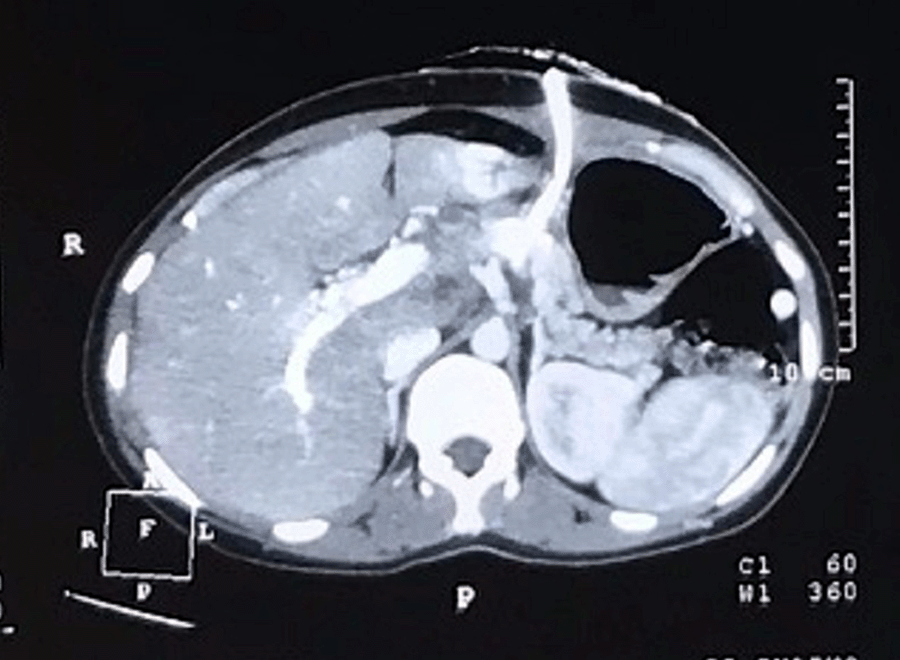

On evaluation, routine hemogram and biochemistry were within normal limits. Serum amylase and lipase were raised three times beyond normal. Pancreas protocol triphasic contrast-enhanced computed tomography (CECT) and contrast-enhanced magnetic resonance imaging (MRI) of the abdomen with cholangiopancreatography (MRCP) showed a large unilocular cystic lesion measuring 8.4 × 6.4 cm with non-enhancing thickened walls in the region of pancreatic neck and body (Figure 1). There was no evidence of calcifications, septations, or mural nodularity. Pancreatic parenchyma adjoining the cyst was atrophic, with some normally enhancing pancreas preserved near uncinate and tail regions. No peripancreatic fat stranding or post-inflammatory sequelae were noted. The main pancreatic duct (MPD) was prominent towards the tail, with no observed communication with the cyst (Figure 2). Multiple necrotic periportal and peripancreatic lymphadenopathy were also noted. A working diagnosis of pancreatitis, secondary to suspected cystic neoplasm of the pancreas, was made.

Figure 1. CECT Scan Axial Cuts Showing Large Cystic Lesion in Pancreatic Neck and Body. Published With Permission

Note. Thickened unenhanced walls and absence of mural nodularity.